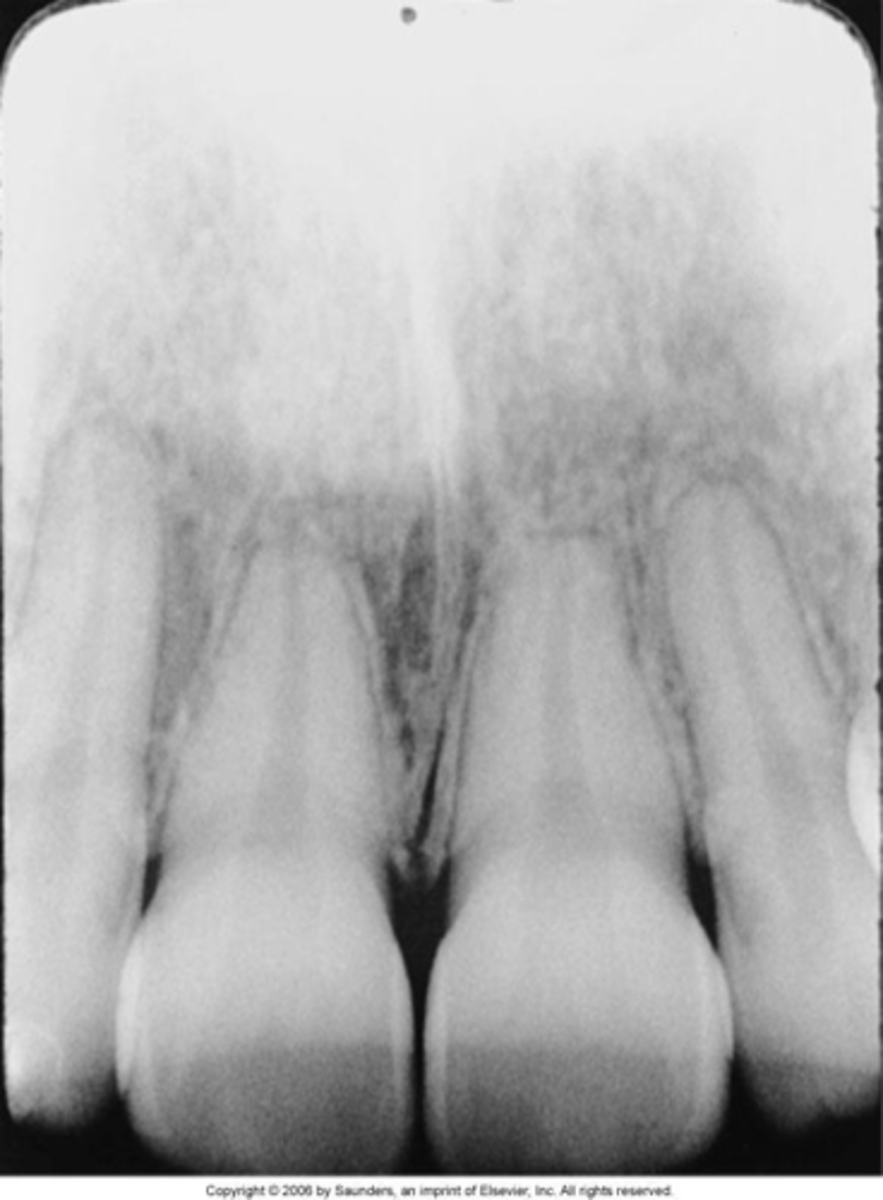

foreshortened images

teeth appear short with blunted roots

caused by too steep vertical angulation

elongated images

teeth appear long and distorted

vertical angulation too flat